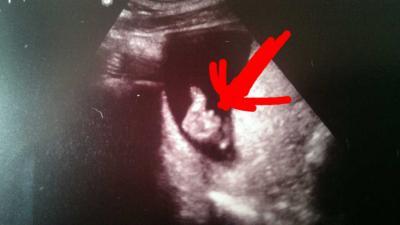

Hey hat jemand von euch auch schon ein Outing...Also bei uns war definitiv ein Schnippi zu sehen...jipppoiiiii nachdem wir ja ein Mädchen haben freuen wir uns tierisch auf einen Jungen

Glückwunsch :) Aaaaber - das ist so ein kleiner Schnippi da - könnte das nicht trotzdem ein Mädchen sein? Also muss man da so früh nicht schauen, ob der hoch oder runter zeigt?

Das kann ich dir nicht genau sagen aber ein Mädchen und da wusste ich in der 17ssw das es ein Mädchen ist....das ist von unten...Weiß nicht ob da was stehen muss oder nicht

Der Schniepel vom Jungen zeigt wohl eher nach oben und der Schniepel vom Mädchen eher waagerecht zum Körper.

stimm ich dir zu. Mädchen haben ebenfalls einen Zipfel. Bei Mädchen zeigt der 30° nach unten & bei einem Jungen eben 30° nach oben.